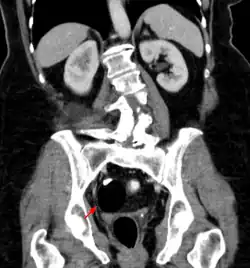

Beyond the newborn period, symptoms of a teratoma depend on its location and organ of origin. Ovarian teratomas often present with abdominal or pelvic pain, caused by torsion of the ovary or irritation of its ligaments. A recently discovered condition where ovarian teratomas cause encephalitis associated with antibodies against the N-methyl-D-aspartate receptor antibody (NMDAR) - often referred to as "anti-NMDA receptor encephalitis", was identified as a serious complication. Patients develop a multistage illness that progresses from psychosis, memory deficits, seizures, and language disintegration into a state of unresponsiveness with catatonic features often associated with abnormal movements, and autonomic and breathing instability.[34] Testicular teratomas present as a palpable mass in the testis; mediastinal teratomas often cause compression of the lungs or the airways and may present with chest pain and/or respiratory symptoms.

Adequate follow-up requires close observation, involving repeated physical examination, scanning (ultrasound, MRI, or CT), and measurement of AFP and/or βhCG.[54][55]